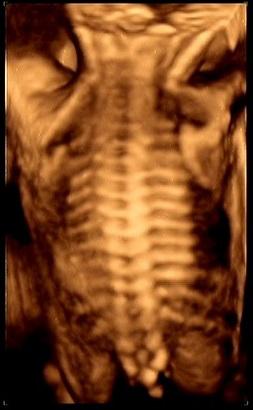

胎儿四维彩超主要是 观察宫内胎儿的生长发育情况,筛查胎儿畸形,为早期诊断胎儿先天性体表畸形和先天性心脏疾病提供准确的科学依据,主要包括以下方面:

2.神经系统畸形: 如无脑儿、脑积水、小头畸形、脊柱裂、脑脊膜膨出等。